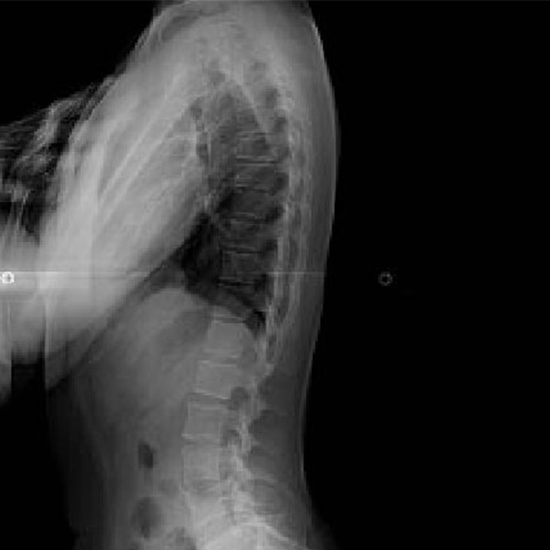

x-ray dorsal spine lateral

What is an X-ray Dorsal Spine Lateral View Test?

The X-Ray Dorsal Spine LAT View finds out what's causing severe back pain and looks for broken or hurt spinal bones (vertebrae). Find any tumors, arthritis, osteoporosis, or spinal infections that might be there. Also, check if the spine has any unusual curves, such as lordosis, kyphosis, scoliosis, or birth defects.